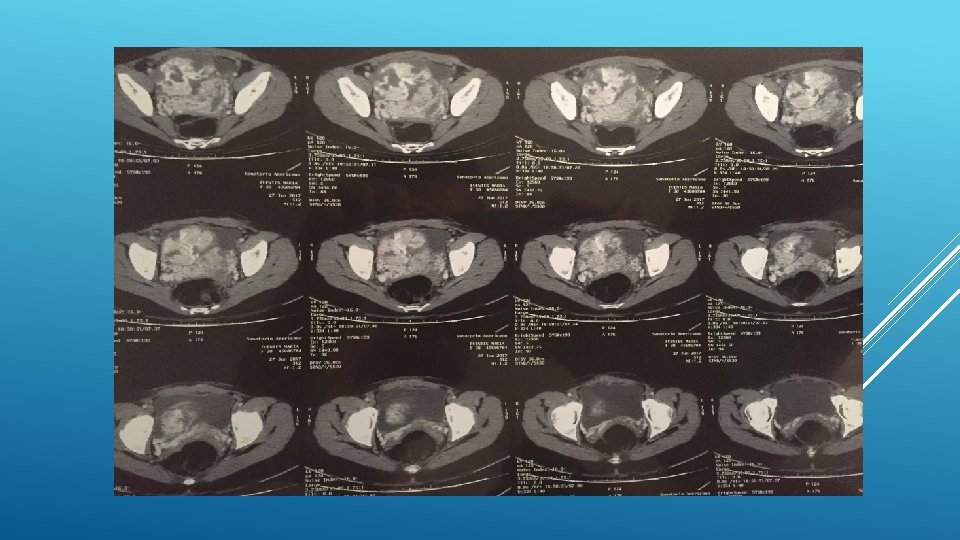

13/6/17 INGRESA A SANATORIO AMERICANO 30 SEMANAS EG, IMPRESIONA SIGNO ACOLCHONAMIENTO, METRORRGIA ACTIVA ESCASA. SIN REPERCION MATERNO FETAL. HEMOGRAMA: HEMOGLOBINA 13, 6 ECOGRAFIA INGRESO: 29 SEM, FULC, PFE 1420 gr, LA normal. PLACENTA OCLUSIVA TOTAL , PRESENTA UN SECTOR DEL ESPACIO RETROPLACENTARIO QUE IMPRESIONA NO CONSERVADO. SE VISUALIZAN LAGUNAS VASCULARES AL UTIILIZAR DOPPLER COLOR EN DICHO SECTOR. NO SE DESCARTA ACRETISMO PLACENTARIO. INGRESA A SALA CONDUCTA EXPECTANTE. 15/6 PERSISTENCIA DE METRORRAGIA ACTIVA, ASOCIANDO REPERCUCION HEMATOLOGICA (HB 9, 9) CON UN PROBABLE ACRETISMO PLACENTARIO SE DECIDE INTERUPCION DE LA GESTACION MEDIANTE OPERACIÓN CESÁREA.

CESÁREA: SE COSTATA PLACENTA PERCRETA EN ESPACIO VESICOUTERINO, HISTEROTOMIA SEGMENTARIA ALTA, SE EXTRAE FETO SM EN PODALICA VIGOROSO. SE COMPRUEBA PLACENTA PREVIA OCLUSIVA TOTAL QUE ATRAVIESA PARED UTERINA. SE LIGA CORDON Y SE DECIDE HISTERECTOMIA.

48 HS INGRESADA EN CTI, BUEN EVOLUCION INGRESA A SALA. BUENA EVOLUCION EN SALA, REQUIRIENDO TRANSFUCION DE GR, HIERRO IV Y EPO. SE REALIZO ATB PROFILACTICA Y SE COMIENZA TROMBOPROFILAXIS AL 6 TO DIA DEL PO. ECOGRAFIA 20/6 NORMAL. SE OTORGA ALTA 26/6 27/6 REINGRESA POR CUDRO SINCOPAL. SE DESCARTO TEP MEDIANTE ETT Y ANGIOTAC: PELVIS EN LECHO QUIRURGICO , COLECCIÓN HETEROGENEA CON IMPORTANTES AREAS DE SANGRADO ACTIVO DE APROX 101 X 100 X 90. LA MISMA COMPRIME VEJIGA.

TAC 16/8 A NIVEL PELVIANO SUPERIOR Y POSTERIOR A VEJIGA COLECCIÓN HIPODENSA, DENSIDAD SIMILAR AL LIQUIDO, PRESENTA BURBUJAS AEREAS EN SU INTERIOR. MIDE APROX 86 x 87 x 63 mm. VEJIGA CONTORNOS REGULARES Y DENSIDAD HOMOGENEA, FONDO DE SACO DE DOUGLAS LIBRE. NO SE OBSERVAN ADENOMEGALIAS PELVICAS. CONTINUA EN CONTROL AMBULATORIO CON ONCOLOGIA Y GINECOLGIA.